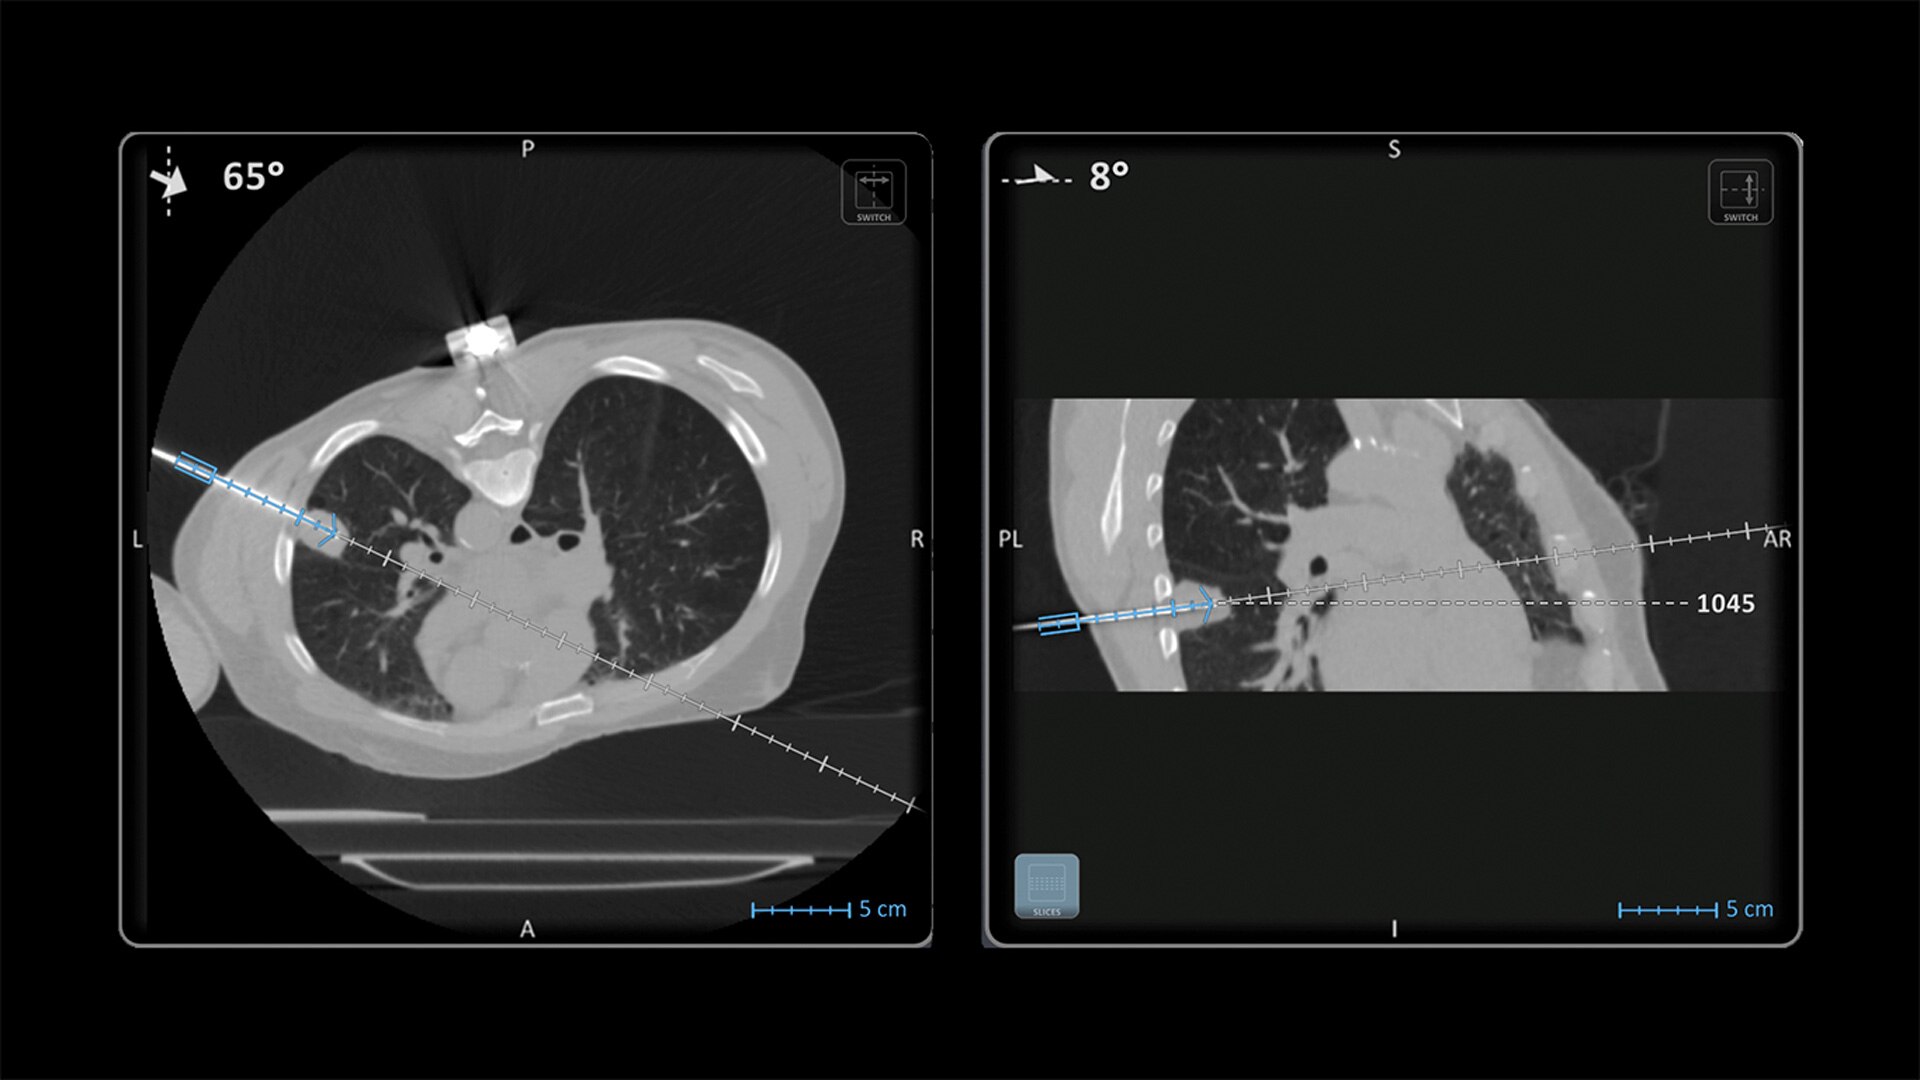

Imactis® CT-Navigation™

Planning and navigation solution for interventional percutaneous radiology.

Imactis® CT-Navigation™ is an electromagnetic (EM) navigation solution for CT-guided percutaneous procedures

Imactis® CT-Navigation™ is designed to radically improve efficiency of Interventional procedures for clinicians and hospitals by increasing their accuracy.